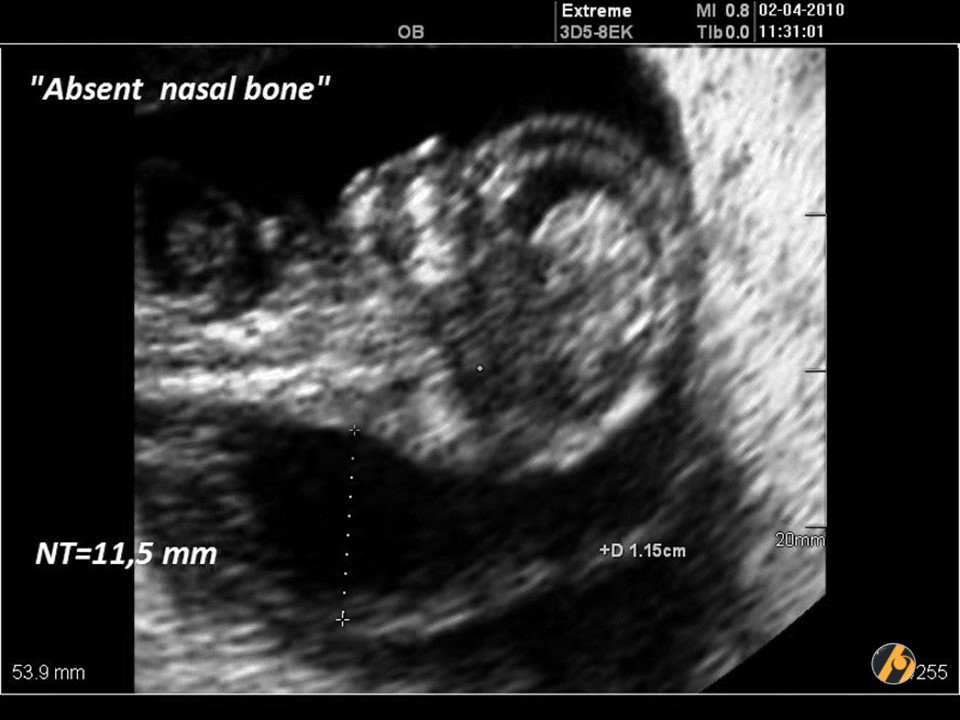

Nosna kost

Za procjenu nosne kosti fetusa, gestacija treba biti 11 + 0 do 13 + 6 tjedana, a CRL 45-84 mm.

Smatra se da je nosna kost prisutna ako je ehogenija od kože i odsutna ako nije vidljiva ili je njezina ehogenost ista ili manja od one na koži.

Odsutna nosna kost

Sa 11-13 tjedana nosne kosti nema u:

- euploidnih fetusa 1-3%

- fetusa s trisomijom 21 60%

- fetusa s trisomijom 18 50%

- fetusa s trisomijom 13 40%

Procjena nosne kosti poboljšava izvedbu kombiniranog probira povećavajući stopu otkrivanja s 90% na 93% i smanjujući lažno pozitivnu stopu s 3% na 2,5%.